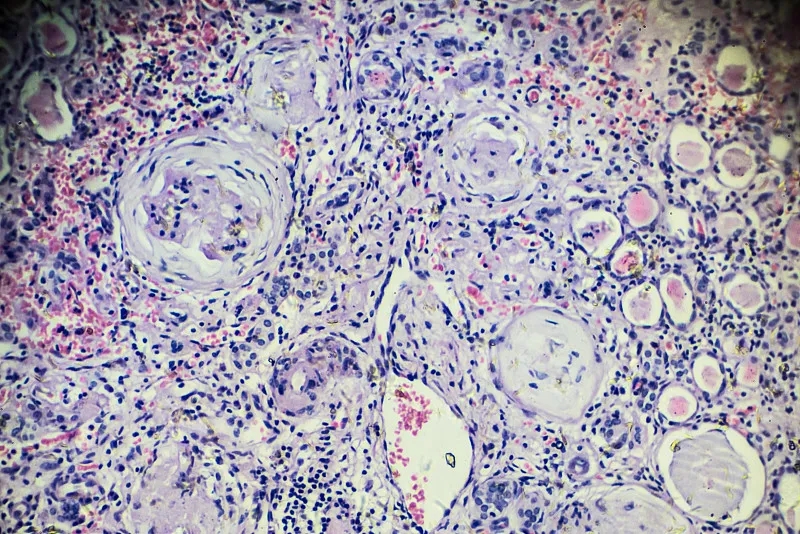

大約10%的MM患者在診斷時還患有CKD或急性腎損傷 (AKI),幾乎50%的MM患者在某個時候經歷過CKD或 AKI。大約10%的MM患者會出現需要長期透析的晚期 CKD,而腎功能損害 (RI) 與MM患者的死亡率和發病率較差有關。

估計腎小球濾過率 (eGFR) 決定腎功能狀態,根據移植時的以下eGFR范圍將患者分為4組: 第1組(7%的患者)的eGFR低于30mL/min/1.73m2,第2組(11%的患者)的eGFR為30至59mL/min/1.73m2,第3組(46% 的患者)的eGFR為60至89mL/min/1.73m2,并且第4組(36%的患者)的eGFR至少為90mL/min/1.73m2。所有370名患者在移植時都有eGFR數據,328名患者有移植后100天的數據,307名患者有移植后1年的數據。